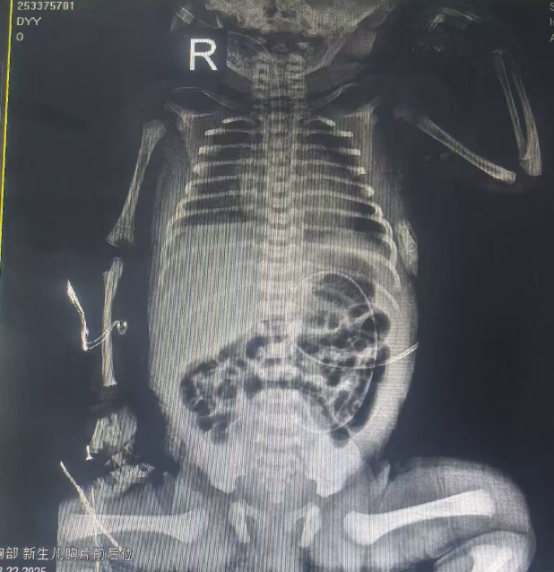

入院后,小雪儿病情迅速恶化。即便在无创呼吸机辅助通气下,末梢血氧饱和度仅维持在70%-80%,肤色苍白如纸。结合临床表现,救治团队高度怀疑胎母输血可能,且已出现失血性休克迹象。医护人员迅速行动——建立静脉通路、完善血常规、胸部正位片、溶血实验、输血前四项及甲胎蛋白等相关检查,一场与时间赛跑的生命救援全面展开。

在新生儿科副主任医师张东平的带领下,主治医师贾毅、主管护师武佩佩、护士居姣姣及唐荣等护理骨干迅速组成救治小组,全力投入救治。检查结果令人揪心:新生儿正常血红蛋白值为170-220g/L,而小雪儿的血红蛋白仅为正常值的五分之一,极重度贫血合并心力衰竭,脑钠肽高达89136pg/ml!

抢救刻不容缓。团队果断实施交叉配血、气管插管、脐静脉置管、腋动脉置管等一系列抢救措施,同时精准纠正休克、输注红细胞悬液。整个救治过程如履薄冰——每一毫升的输液输血都需精确计算,多一分可能加重心衰,少一分则无法逆转休克与贫血。